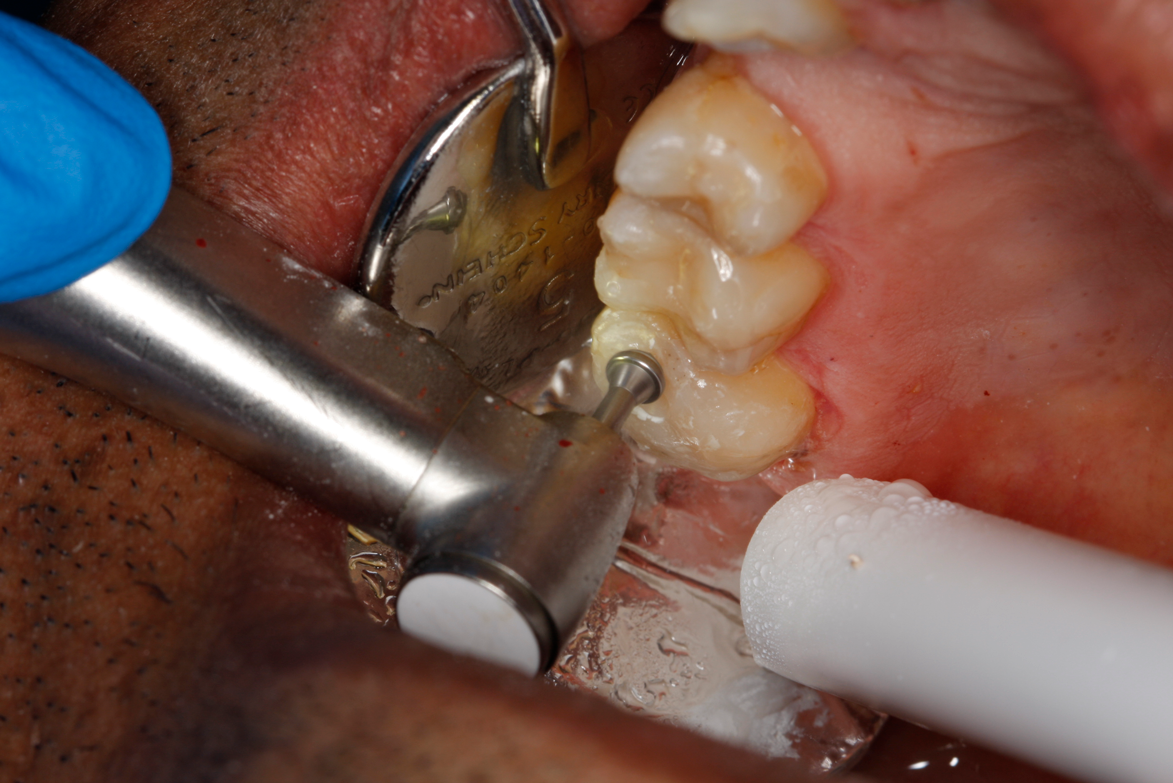

Figure 8A is a radiograph revealing deep root caries previously restored temporarily by a resident at the AEGD Residency Program clinic with glass ionomer utilizing a lateral rather than occlusal approach. After the glass ionomer failed to adhere, another resident again attempted a lateral approach that resulted in the restoration shown in Figure 8B. A third resident had success with an occlusal approach, removing a failed occlusal composite to access the distal  (Figure 9). This attempt was successful both in the preparation of the lesion and in the placement of a dual- cure bulk-fill flowable (Bulk EZ Plus, Zest Dental Solutions; alternatively: HyperFIL®, Parkell; Fill-Up!, Coltene) extruded through a bendable needle (Figure 10). Figure 11 shows the final preparation after tissue removal was accomplished with rotary gingitage; note that this was performed with the rubber dam in place. An air abrasion device (Groman Etchmaster, Groman Dental; alternatively: PrepStart H2O, Zest Dental Solutions; Bioclear Blaster, Bioclear) was used with potassium bicarbonate to remove biofilm prior to acid etching (Figure 12). Phosphoric acid 37% was utilized in a total etch fashion (Fig- ure 13 and Figure 14) for 20 seconds. Figure 15 shows the universal bond (Scotchbond Universal, 3M; alternatively: All-Bond Universal®, BISCO; Prelude One, Danville Materials) with metha- cryloyloxydecyl dihydrogen phosphate (MDP) being scrubbed into the cavity for 20 seconds. After air thinning for 20 seconds, the adhesive was light cured for 40 seconds at 1,200 mw/cm2power density (Figure 16).

Fig 12. Utilizing particle blasting with a microetcher loaded with potassium carbonate to remove biofilm in the cavity and margins.

Figure 12

Fig 13. Total etch with 37% phosphoric acid.

Figure 13